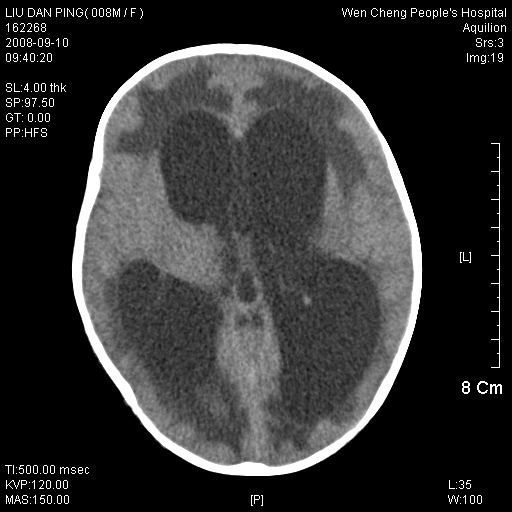

以下是引用卜一在2008-9-10 16:21:00的发言:[br]髓母细胞瘤伴梗阻性脑积水!支持![br]髓母细胞瘤特点:—般直径大于3.5cm,位于后颅凹中线之小脑蚓部。累及上蚓部的肿瘤延伸到小脑幕切迹之上,ct平扫肿瘤多呈均匀一致的高或等密度病灶,增强检查呈均匀一致的强化。病灶中有小坏死时,平扫亦可呈不均匀之混杂密度,注药后有增强。[br]

以下是引用zjzjr在2008-9-10 15:09:00的发言:[br]髓母细胞瘤伴梗阻性脑积水.